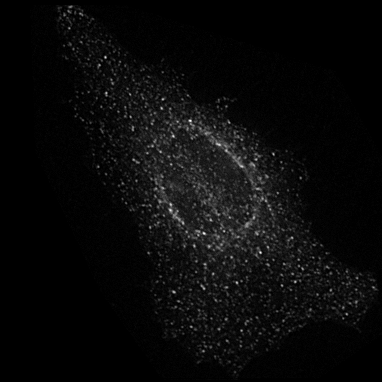

Microscopy techniques are employed to capture subcellular localization images of proteins in a cell, which were previously analyzed using traditional wet methods. However, advances in microscopy techniques have brought an avalanche of medical images in a considerable amount; hence, manual analysis and processing of these medical images become nearly impossible for biologists. Moreover, a subjective inspection of images may lead to errors in decision-making process shao2017deep ; tahir2011protein ; kreft2004automated . It is highly likely that the images generated for proteins of the same class may look visually different (see Figure 1). Similarly, proteins belonging to two different classes may look alike. Such a situation leads to the poor performance of classification systems. These problems are resolved by applying different hand-crafted feature extraction strategies to capture multiple views from the same image tahir2016protein . Hence, this is a cumbersome job and may fail to discriminate with high accuracy.

Prediction confidence: We compare the prediction confidence of traditional classifiers trained on Yeast and HeLa datasets against our PLCNN on four images as shown in Figure 11. Each image has the prediction probabilities for each algorithm underneath. The red color shows when the prediction is incorrect, whereas the green is for the correct outcome. It can be observed that our method predicts the correct labels with high confidence, while the probability is very low when the prediction is incorrect. The image in the first column in Figure 11 is very challenging due to minimum texture and almost no structure. All the methods failed to identify the type of protein in the mentioned image correctly. However, the competing methods prediction scores are much higher than ours. Similarly, our algorithm confidence is always high when the prediction is correct and low when it is incorrect. This shows the learning capability of our network.